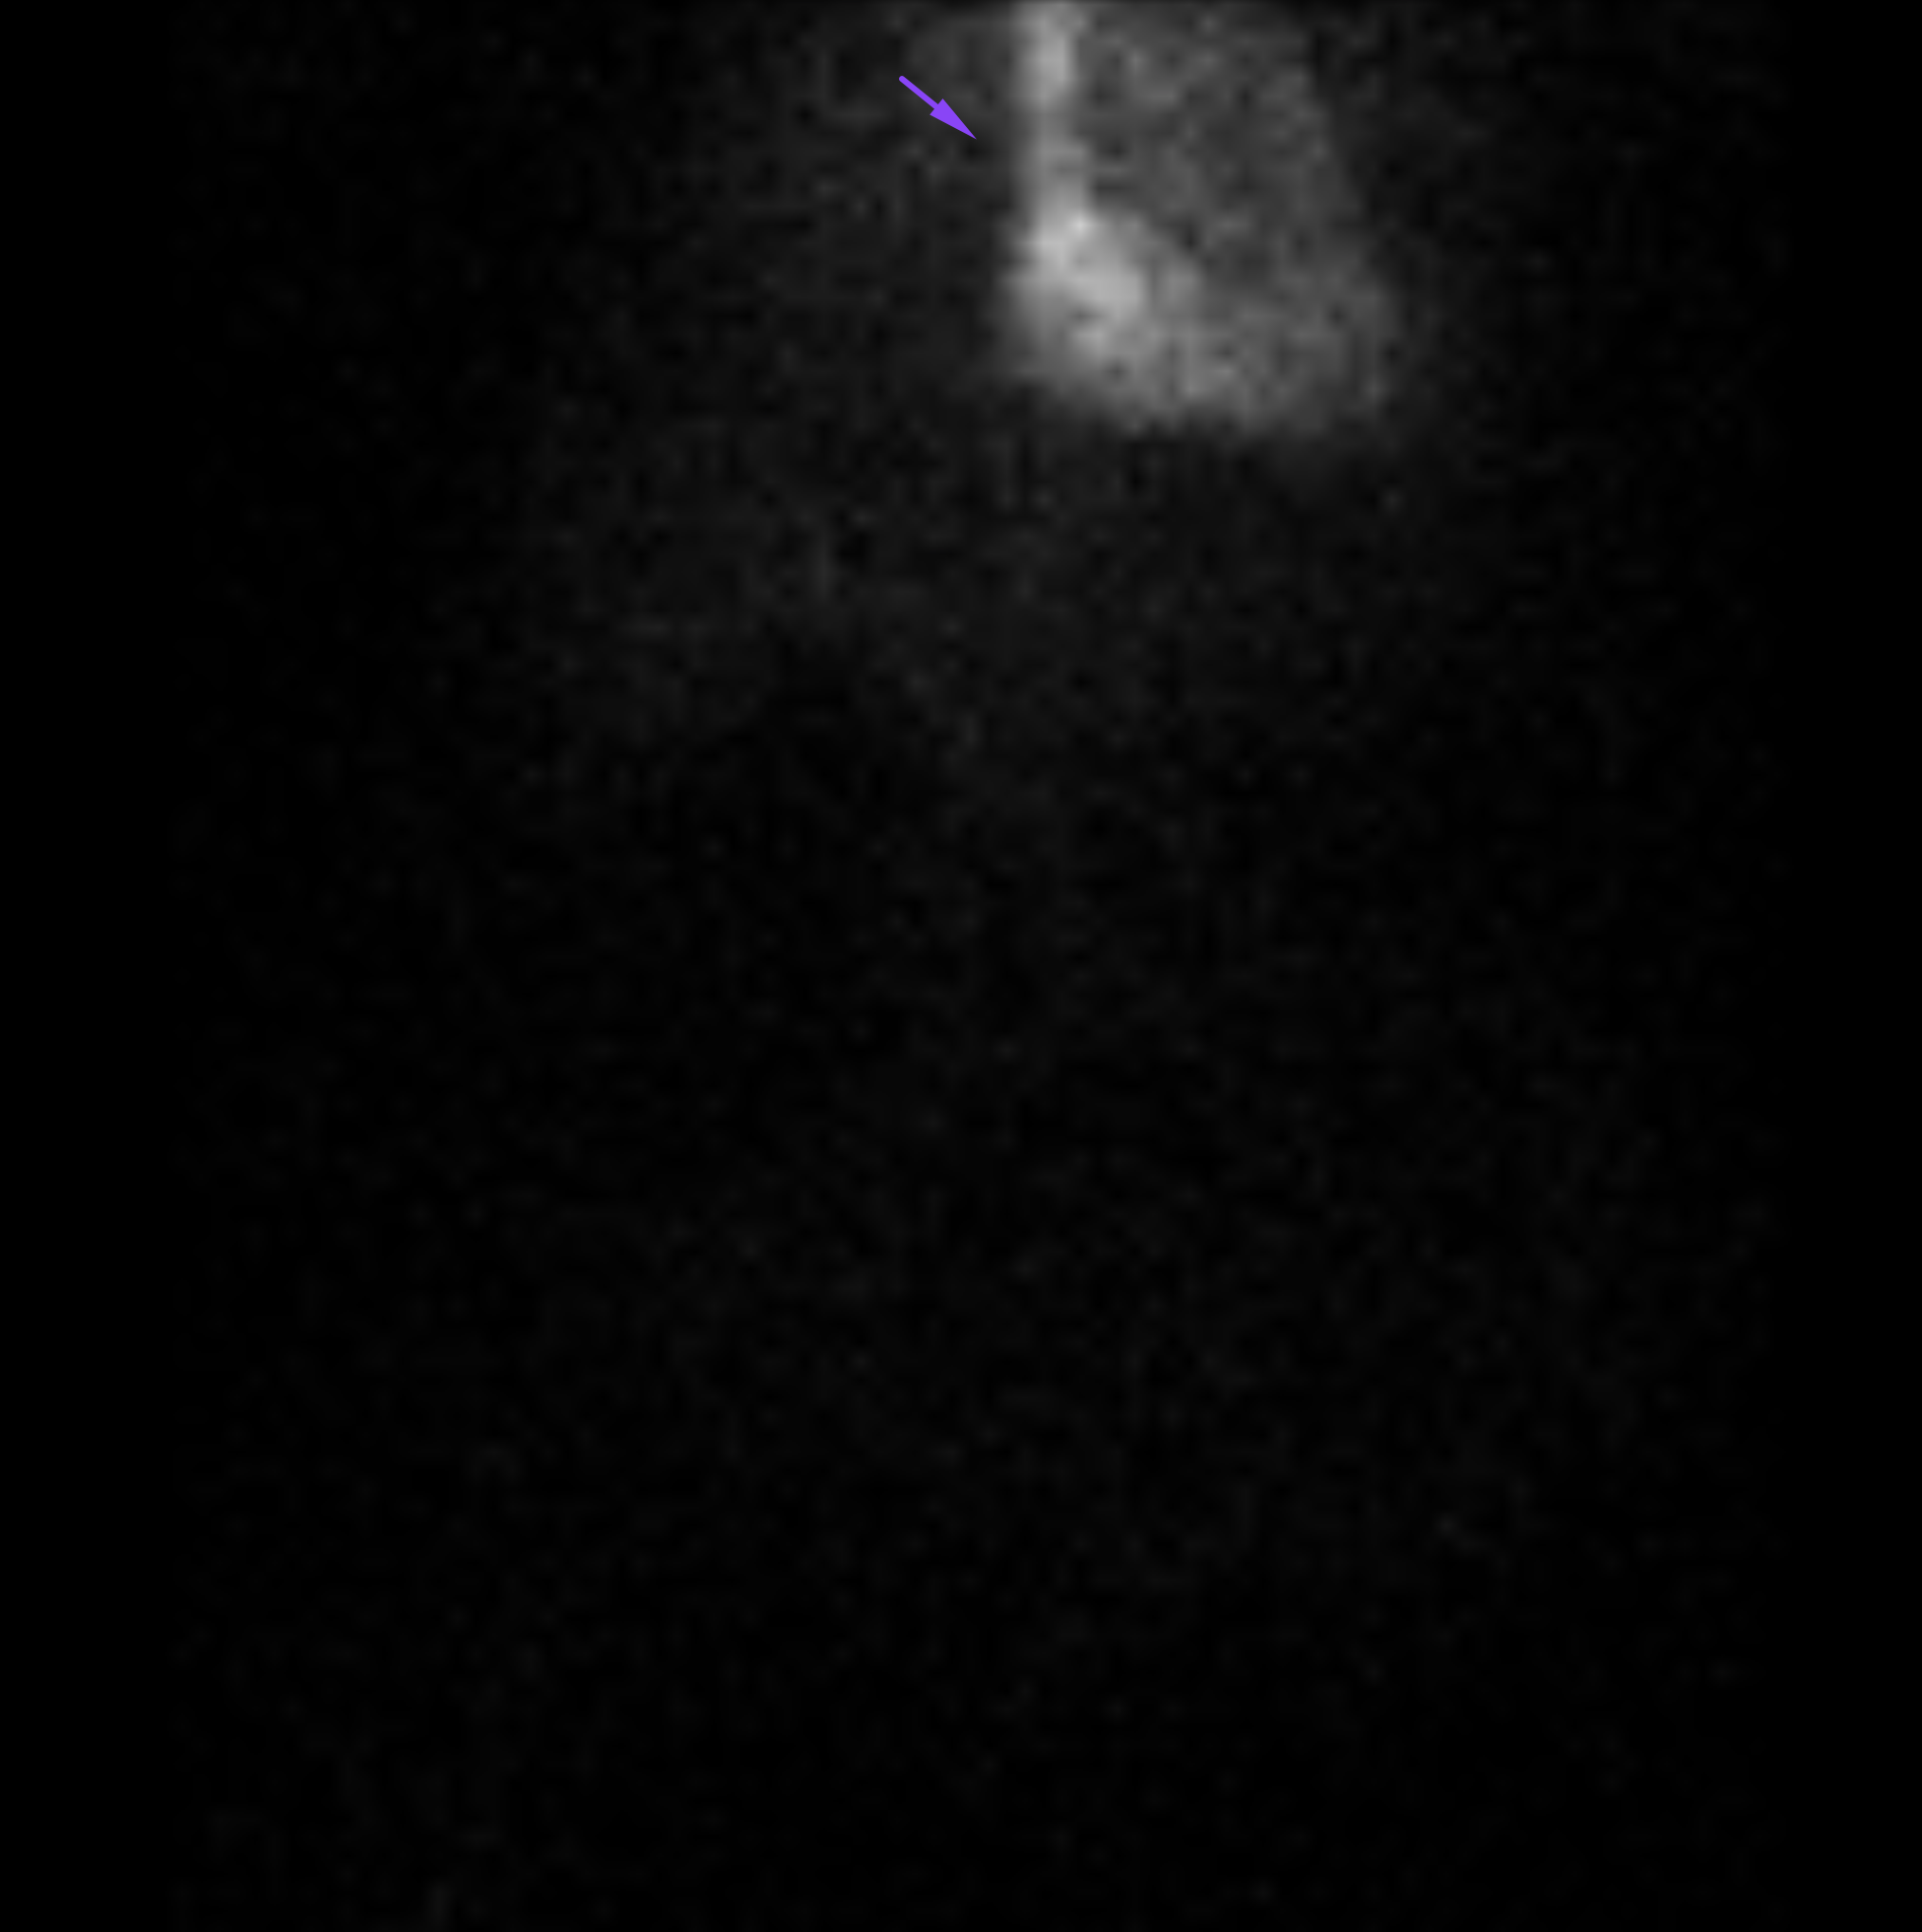

Age: 84

Sex: Female

Indication: Hematochezia with recent negative upper endoscopy and colonoscopy

Radiotracer: Tc99m labeled RBCs

Sample ReportPositive for active GI bleeding, likely originating within small bowel in the left lower quadrant.